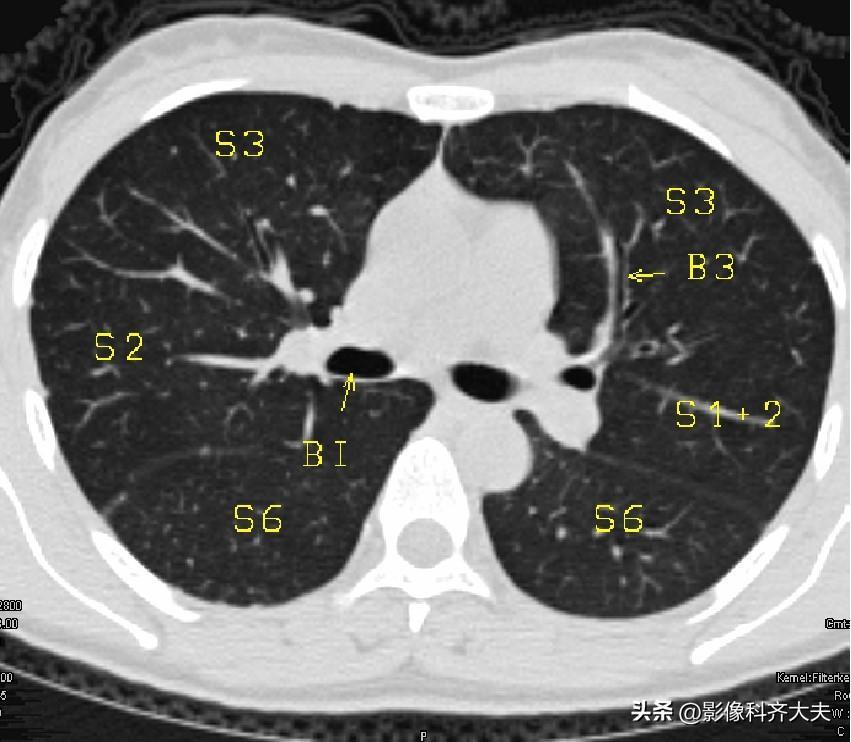

图7-隆突下1cm层面

▲BI:中间支气管